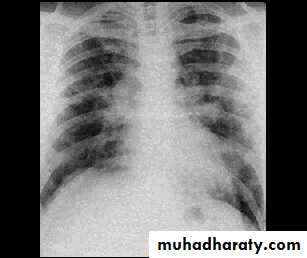

Chest X-rayAcute phase :a fine nodular shadowing

Repeated exposure :fibrotic changes more marked in the upper azones, as with sarcoidosis, than in the lower zones, as with cryptogenic fibrosing alveolitis.

Pulmonary infeltrate